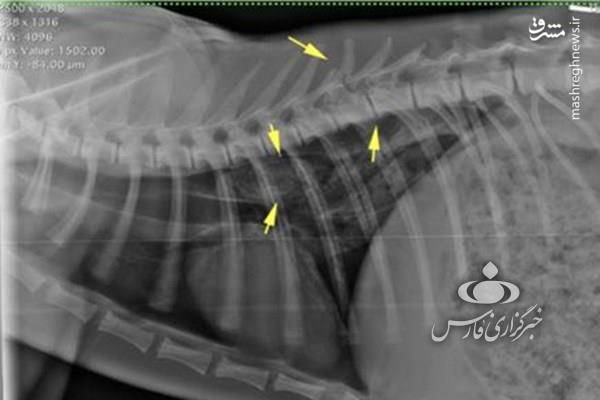

بنابر این گزارش که پس از انجام کالبد گشایی، پاتولوژی، سی ای اسکن و رادیولوژی تنظیم شده است دلایل مرگ یوزپلنگ سمنان به شرح زیر است:

- مهره L5 کمری شکسته و به شدت جابجا شده و مهره T8 سینه شکستگی و جابجایی کمی را نشان می دهد.

- عدم کارایی implant های قرار داده شده در جراحی که پس از آن تکه های کوچک بیشتری از مهره L5 شکسته است.

- تجمع مایع درون حفره شکمی از عوارض بعد از عمل

- ضایعه (پارگی) ریه

همچنین به دلیل عدم انجام اقدامات تشخیصی ازجمله سی تی اسکن و ام آر آی پیش از عمل جراحی، شکستگی مهره T8 و پارکی ریه در جانور تشخیص داده نشده و لذا اقدام درمانی خاصی نیز در این خصوص صورت نپذیرفته.

در نهایت تجمع مایع درون حفره شکمی، خونریزی داخلی و متعاقب آن کم خونی ایجاد شده منجر به مرگ یوزپلنگ شده است.